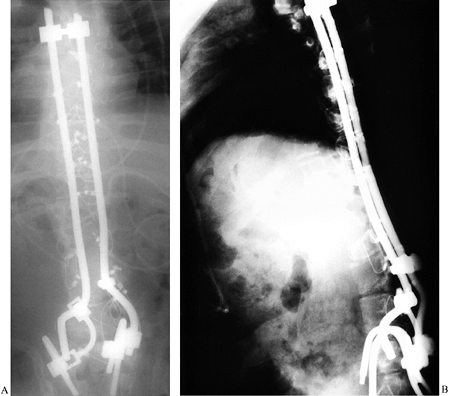

![]() |

Figure 157.3. A:

A 13-year-old boy with a thoracic-level myelomeningocele. He had a severe, progressive right thoracolumbar paralytic curve of 84° and significant pelvic obliquity of 21°. Staged anterior and posterior procedures 1 week apart were necessary to correct the rigid spinal deformity and pelvic obliquity. The combination of an anterior Zielke procedure followed by posterior instrumentation and fusion with a Luque rod with Galveston pelvic fixation provided adequate correction of his deformities (B). |